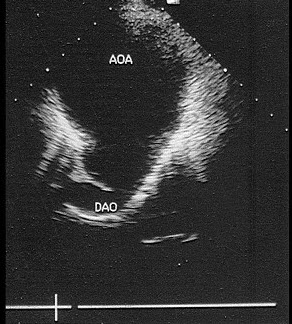

5、单项选择题

该病例最可能诊断()

A.真性动脉瘤

B.假性动脉瘤

C.夹层动脉瘤

D.以上都不是

E.主动脉瓣狭窄